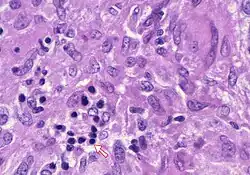

In pathology, a Councilman body, also known as a Councilman hyaline body or apoptotic body, is an eosinophilic globule of apoptotic hepatocyte cell fragments. Ultimately, the fragments are taken up by macrophages or adjacent parenchymal cells.[1] They are found in the liver of individuals suffering from acute viral hepatitis, yellow fever, and other viral syndromes.[2]

With a bright field microscope, Councilman described typical, discrete, necrotic lesions in human hepatic cells of those infected with yellow fever.[9] He noted that the bodies appeared to be red in hematoxylin and eosin-stained sections of hepatic tissue, while being circumscribed, varying in size, round or irregular shape, and having numerous vacuoles of different sizes.

Five adults with hepatitis, two children with hepatoma, and three mongrel dogs provided tissue samples for study have an auxiliary liver transplant into the pelvis. The tissues were fixed immediately in ice-cold 1% osmium tetroxide, buffered with veronal acetate, and sucrose. Sections were cut, stained with lead hydroxide or citrate, and viewed under an electron microscope. The results showed the both canine and human tissue were intact, but altered hepatocytes were observed.[11] The doctors declared that councilman bodies were observed as vacuolated acidophilic bodies within the tissue samples.